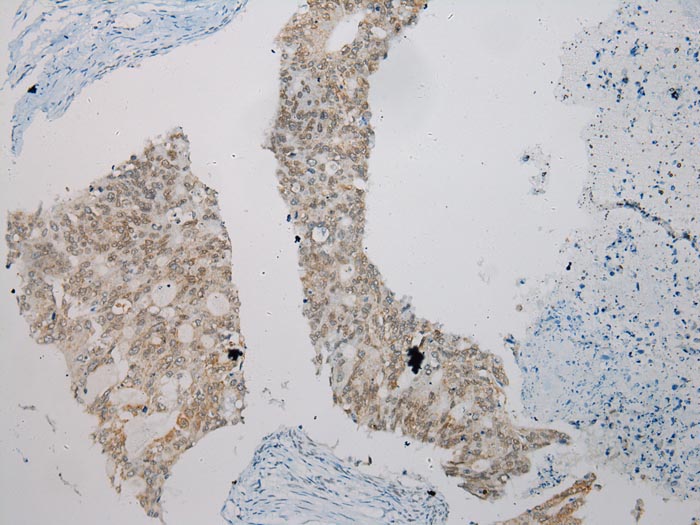

Immunohistochemical analysis of paraffin-embedded Human Colorectal cancer tissue using #43434 at dilution 1/200.